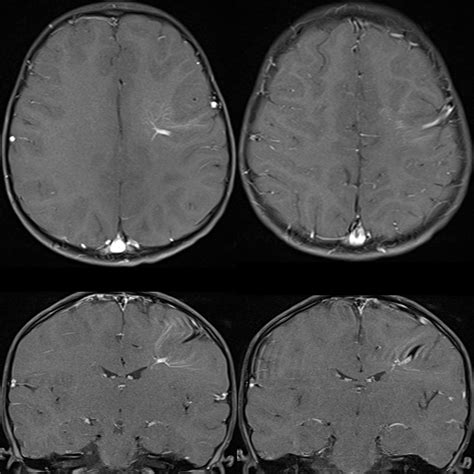

Learn about a Developmental Venous Anomaly (DVA), a common congenital brain vascular malformation. Discover why these benign venous variations are typically asymptomatic, how they appear on MRI or CT scans, and when neurosurgeons consider them clinically significant. Understand the risks and characteristics of this incidental vascular finding to better navigate your neurological health and diagnostic imaging results.